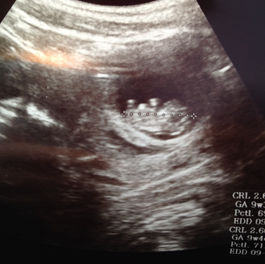

Well, here we go again.

Here's what happens when you think you can't get pregnant without thyroid medication and then find out that you're almost through your...